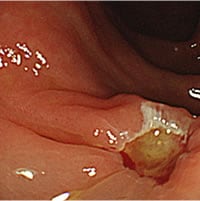

大腸ポリープ(NBI、狭帯光拡大観察)

ポリープとは粘膜の表面に盛り上がってできるもので、病名ではなく形態を示します。ポリープには良性のものと悪性のものがあり、大腸の場合は良性と言っても悪性化することのない過形成性ポリープと、見つかった時は良性でも、そのまま切除せずに放置することで数年後にがんに変わる可能性のある大腸腺腫があります。大腸腺腫ががんに変わるリスクや時期を予測することはできません。大腸カメラ検査での早期検診、がん化する前の段階でポリープを取り除くことが大切です。

大腸カメラを使うとわかる病気とは?